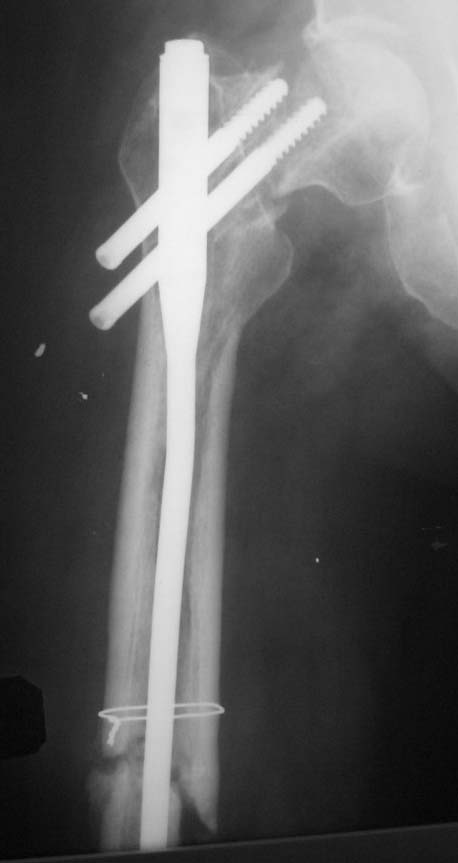

Пациент (мужчина), 34 года. Травма в результате ДТП в апреле 2011 года. Проводилось оперативное лечение – закрытая репозиция, остеосинтез AFN. В октябре 2011 года – декортикация, тунелизация, фиксация отломков верхней трети диафиза бедренной кости проволочным серкляжом, удаление дистального блокирующего винта. На контрольных рентгенограммах определяется миграция шеечных винтов конструкции. Пациент передвигается на костылях с дозированной нагрузкой на ногу (полная нагрузка болезненна в области тазобедренного сустава). Вариант лечения - тотальное эндопротезирование тазобедренного сустава+остеосинтез верхней трети диафиза бедренной кости (ретроградным стержнем ЦИТО, пластиной, АНФ).Жду Ваших комментариев

Вроде признаков асептического некроза головки не видно. Думаю подвертельная остеотомия с устранением варуса с фиксацией 95 гр пластиной + ретроградно стержень с рассверливанием канала.

Добрый день! Думаю, что все предшествующие проблемы из-за некорректной установки данной металлоконструкции. Не надо было добиваться красивой рентгенкартинки используя серкляжи и т.п.. Устранены все виды смещения - этого уже достаточно (один из основных принципов БИОСА сохранение перирефрактурной гематомы, нарушив периоссальную васкуляризацию с интрамедуллярной- получили замедленную консолидацию). К сожалению шеечные винты даже с поправкой на их миграцию тоже утановлены не совсем корректно. Но это по большому счёту бывает у каждого, кто хорошо работает, ошибок нет если ничего не делать. В данной ситуации ставить протез на длинной ножке, убирая из фнкции половину нормальной бедренной кости у молодого 34-х летнего человека считаю абсолютно нецелесообразным. Конечно полной информацией о данном больном не владею, но думаю, что на данном этапе только реостеосинтез, Любой длинный проксимальный вертельный стержень, большего диаметра (Де-пьюшный Афиксус, страйкеровскую Гамму и т.д., принципиального значения не имеет, что возможно в Ваших условиях), с рассверливанием интрамедуллярного канала и корректной установкой шеечных винтов, с выведением нормального шеечно-диафизарного угла и умеренной компрессией на шеечном винте шейки бедренной кости. Установку провести в динамическом варианте и дозированную нагрузку сразу. Думаю проблему с диафизом Вы решите, что касается шейки-решать по мере поступления, если встанет вопрос через некоторое время об энопротезировании, то это будет классический тотальник, без удлинённых ножек, с типичной техникой операции эндопротезирования, что думаю важно для 34-х лет.

Головка вроде еще живая, думаю стоит побороться за сустав. Подвертельная корригирующая остеотомия короткой гаммой или отмоделировать LCP с 2 винтами в шейку. На диафиз LCP MIPO или ретроградный штифт с блокированием.